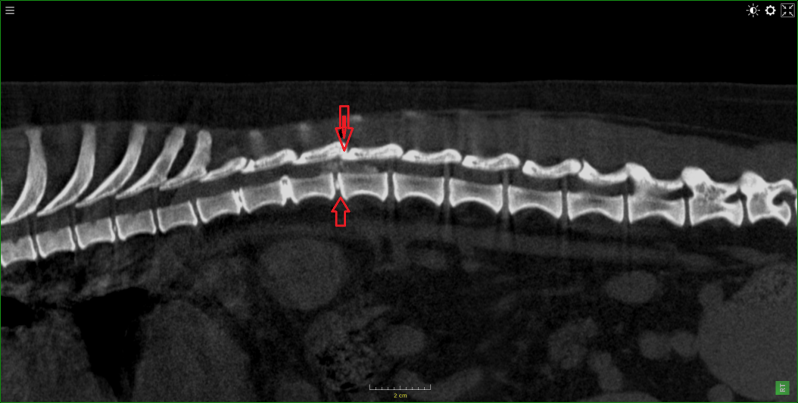

Teckel met discus hernia

Dalmatier van 11 jaar met verlamming ten gevolge van  discus hernia op de overgang van T13  naar L1.

Eerst beelden van RX,  daarna scan beelden met en zonder contrast , vervolgens 3D beeld.